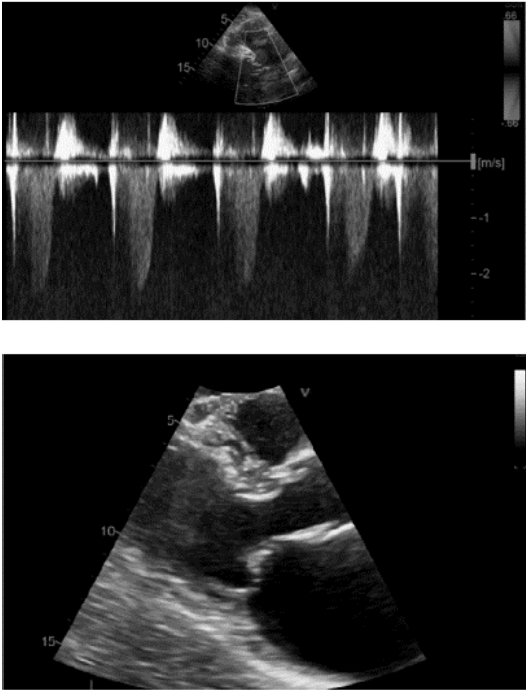

Paciente de 48 anos de idade, sexo feminino, apresenta fibrilação atrial e sopro regurgitativo em foco mitral. Foi realizado ecocardiograma, o qual obteve as imagens abaixo.

Com base nessa situação hipotética, assinale a alternativa correta que apresenta o diagnóstico ecocardiográfico do mecanismo da insuficiência mitral e a classificação de Carpentier.

Imagem: Arquivo pessoal.